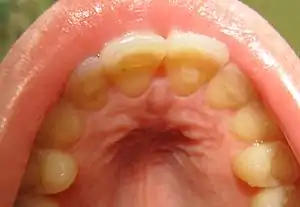

| Loss of enamel (acid erosion) from the inside of the upper front teeth as a result of bulimia | |

- Perimolysis, or severe dental erosion of tooth enamel[17]

People with bulimia are more likely than people without bulimia to have an affective disorder, such as depression or general anxiety disorder. One study found 70% had depression at some time in their lives (as opposed to 26% for adult females in the general population), rising to 88% for all affective disorders combined.[25] Another study by the Royal Children's Hospital in Melbourne on a cohort of 2,000 adolescents similarly found that those meeting at least two of the DSM-IV criteria for bulimia nervosa or anorexia nervosa had a sixfold increase in risk of anxiety and a doubled risk for substance dependency.[26] Some with anorexia nervosa exhibit episodes of bulimic tendencies through purging (either through self-induced vomiting or laxatives) as a way to quickly remove food in their system.[27] There may be an increased risk for diabetes mellitus type 2.[28] Bulimia also has negative effects on a person's teeth due to the acid passed through the mouth from frequent vomiting causing acid erosion, mainly on the posterior dental surface.